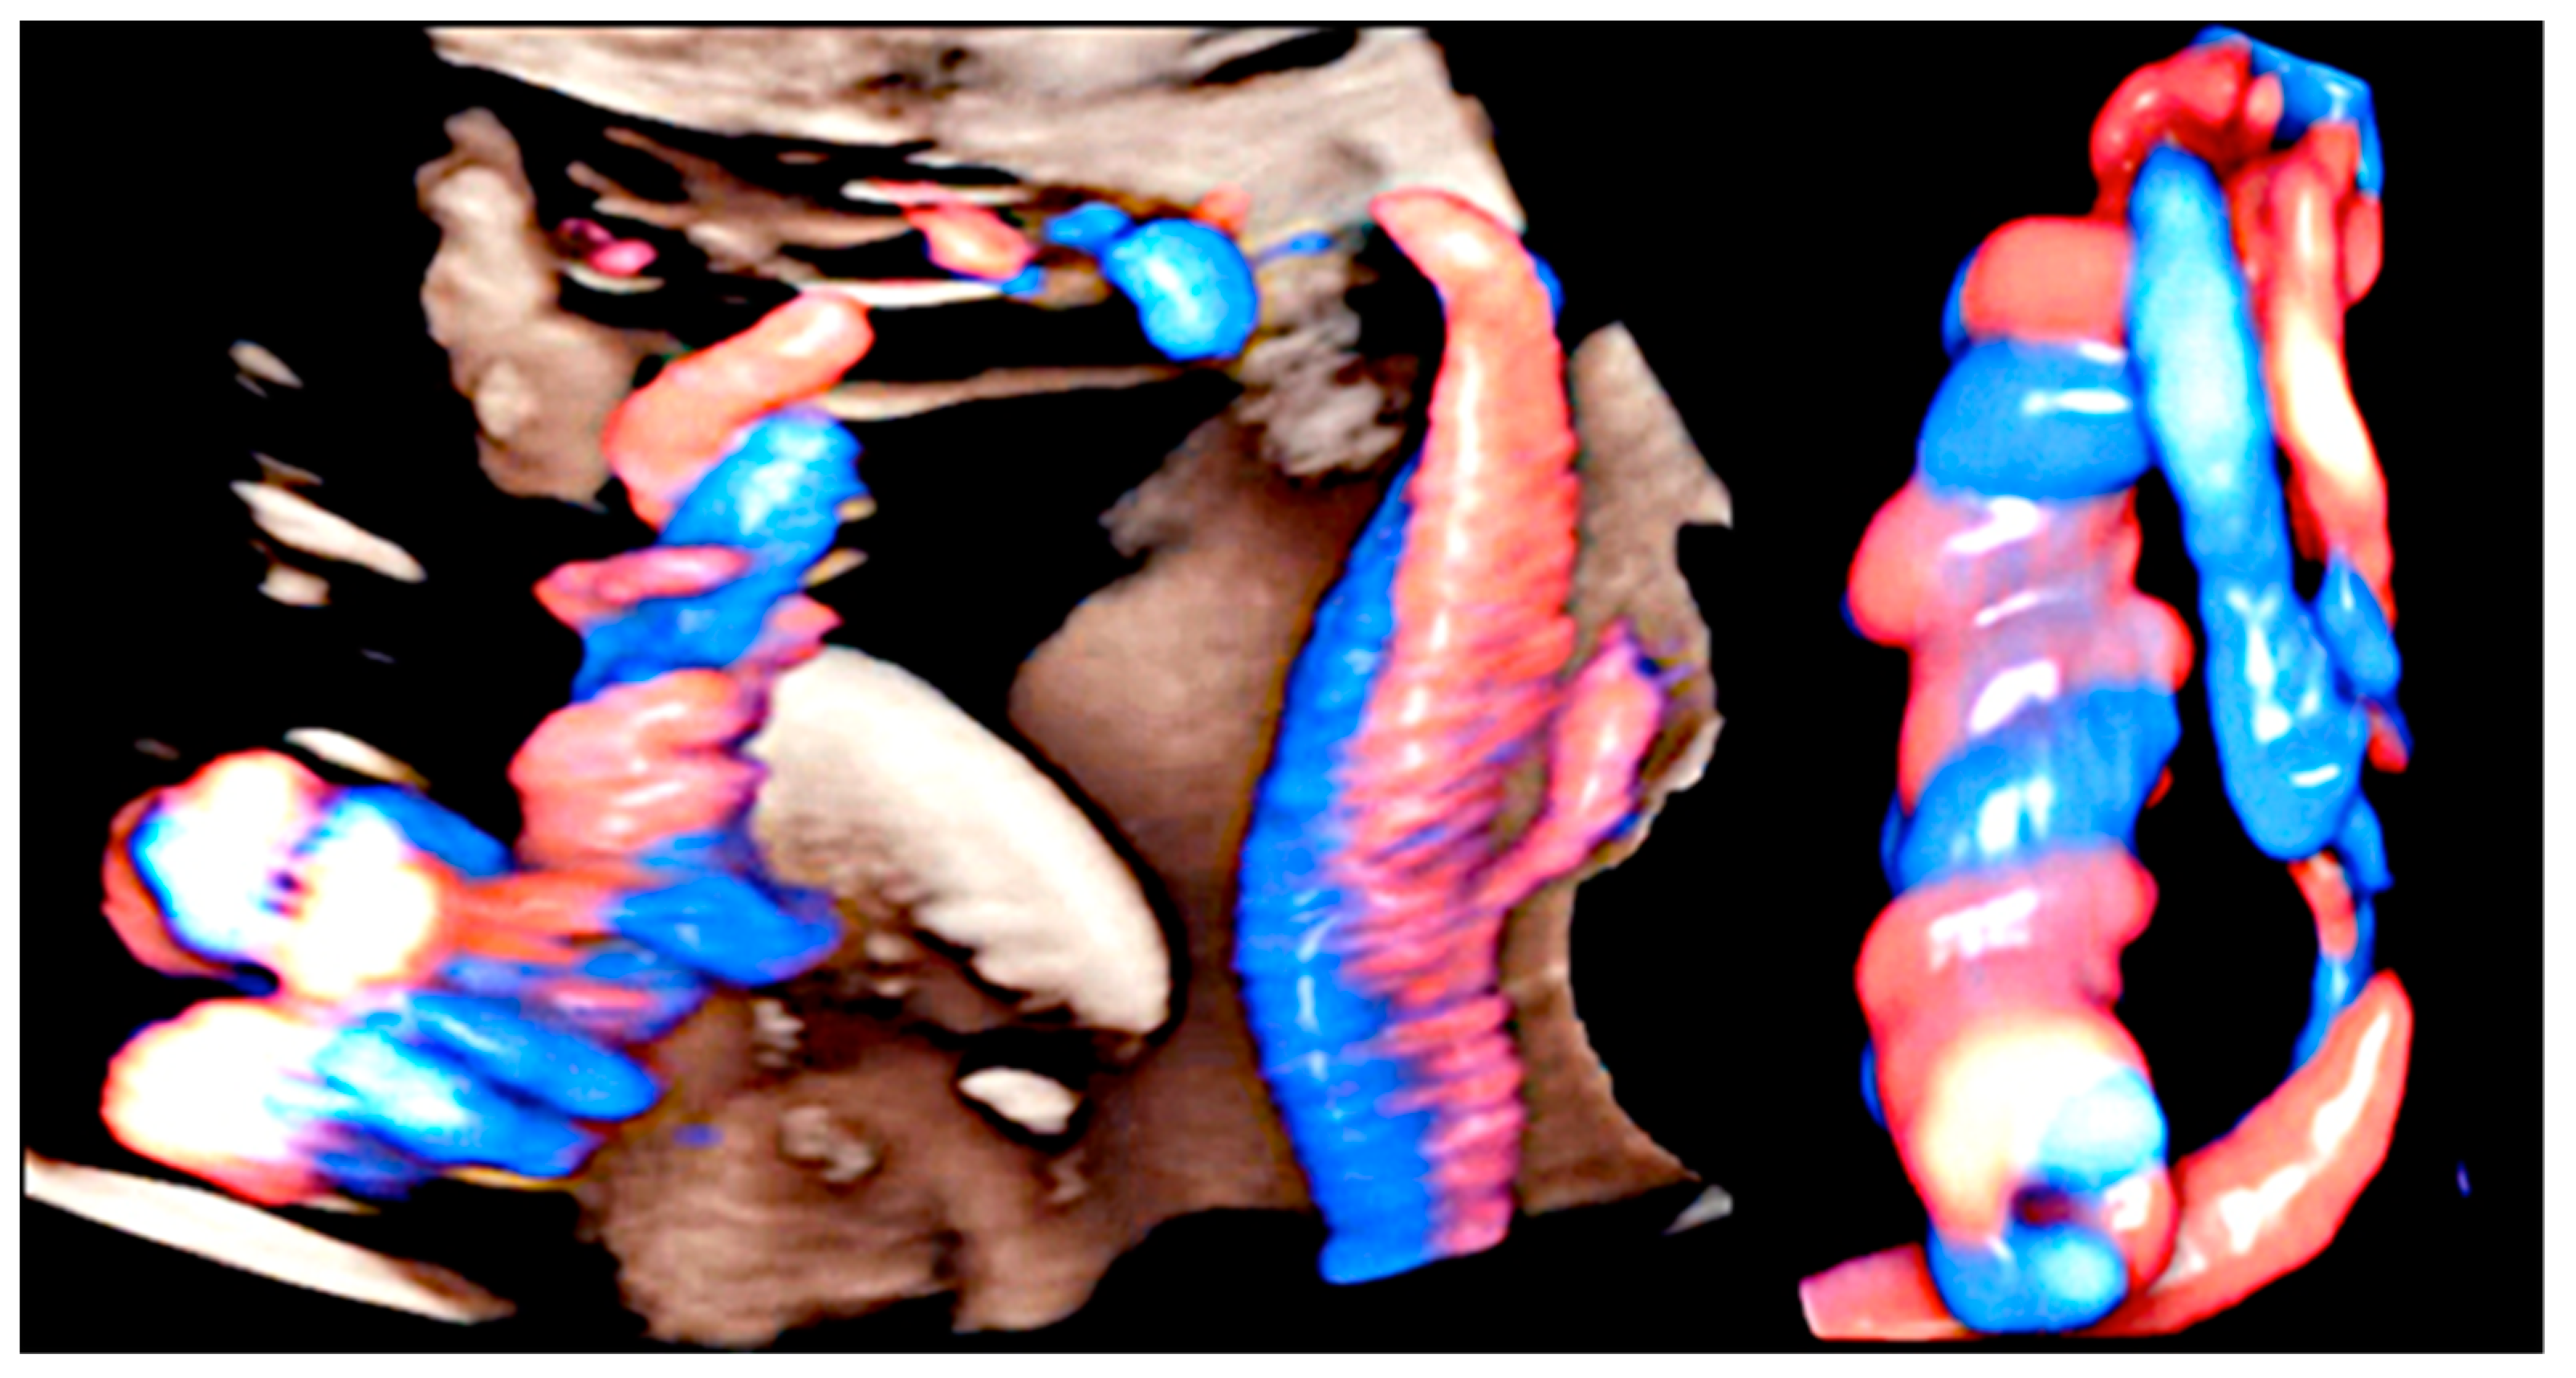

3.2. True Umbilical Cord Knot